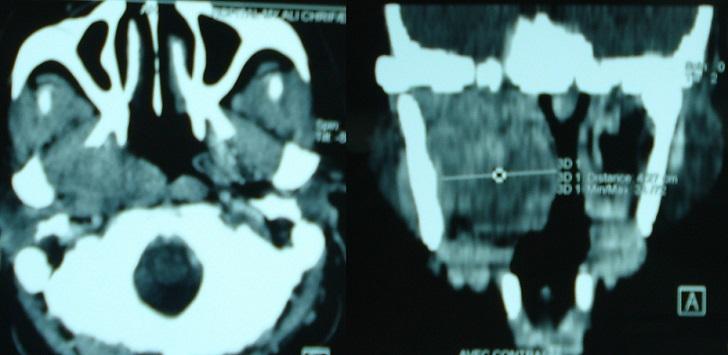

Salivary gland tumors are a relatively rare and morphologically diverse group of lesions. Pleomorphic adenoma is a benign tumor of the salivary gland that consists of a combination of epithelial and mesenchymal elements. The tumor most commonly arises from the parotid (60-70%) or submandibular glands. It develops less frequently in a minor salivary gland, presenting as an intraoral mass depend on the soft palate. We describe a case of benign pleomorphic adenoma of soft palate in a 45 year old female with computed tomography and histopathological findings. This patient presented in ENT department with history of gradually increasing mass lesion in the palatal region over a period of few months.

涎腺肿瘤是一组相对罕见且形态多样的病变。多形性腺瘤是涎腺的一种良性肿瘤,由上皮和间充质成分组成。该肿瘤最常见于腮腺(60 - 70%)或下颌下腺。在小涎腺中发生频率较低,表现为取决于软腭的口腔内肿物。我们描述了一例45岁女性软腭良性多形性腺瘤的病例,伴有计算机断层扫描和组织病理学检查结果。该患者因腭部区域肿物在数月内逐渐增大的病史就诊于耳鼻喉科。